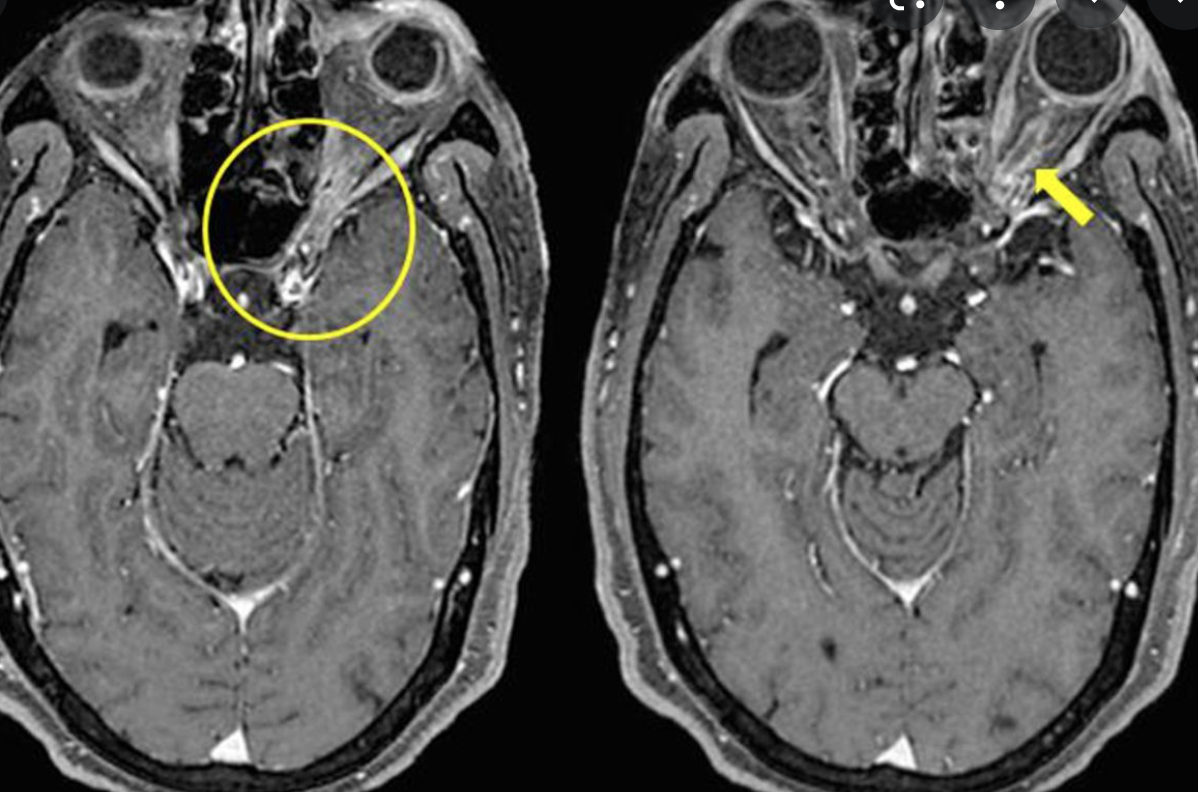

https://www.researchgate.net/figure/Bilateral-Sturge-Weber-syndrome-Postcontrast-axial-MR-image-A-shows-gross_fig1_14472655

Bilateral Sturge-Weber syndrome. Postcontrast axial MR image ( A ) shows gross leptomeningeal thickening and enhancement related to the right hemisphere and less extensive abnormality of the left occipital region. Unenhanced axial T1-weighted image ( B ) shows thickening of the posterior globes bilaterally; after administration of contrast material ( C ), marked enhancement is seen in both globes. Abnormal high signal is present in this region on the proton density–weighted image ( D ). Bilateral, diffuse choroidal hemangiomas were found at ophthalmoscopy (not shown).